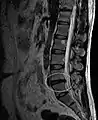

L'imagerie par résonance magnétique peut montrer la hernie, le canal vertébral, les nerfs, les tissus environnants. Les tissus mous sont les mieux analysés par cet examen qui est le plus performant pour le diagnostic de hernie discale. Les images pondérées en T2 montrent clairement la hernie.

IRM lombaire sagittale montrant une hernie discale de niveau L4-L5.